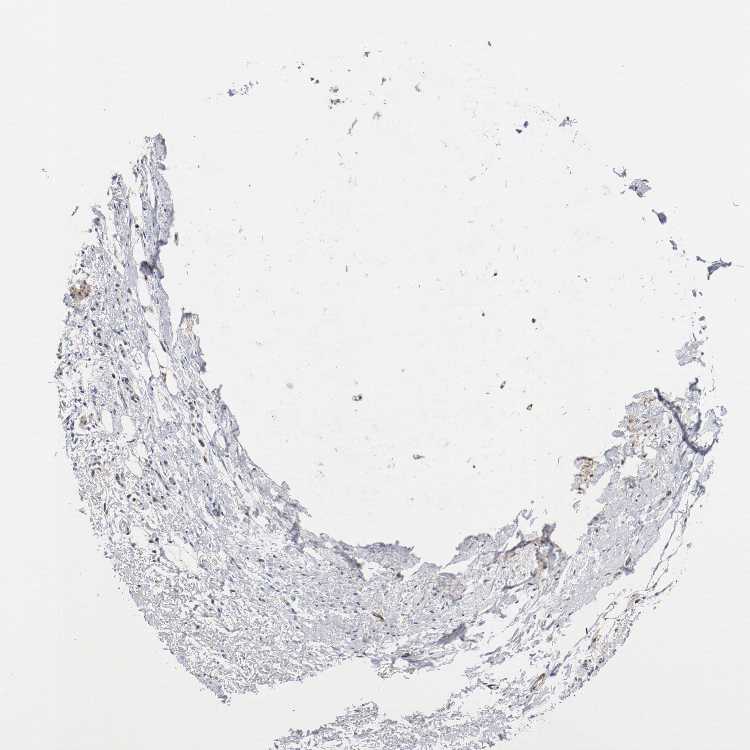

SOFT TISSUE 1 - Antibody stainingi

Antibody staining in the annotated cell types in the current human tissue is reported as not detected, low, medium, or high, based on conventional immunohistochemistry profiling in selected tissues. This score is based on the combination of the staining intensity and fraction of stained cells.

Each image is clickable and will lead to virtual microscopy that enables deeper exploration of all samples and also displays staining intensity scores, fraction scores and subcellular localization as well as patient and tissue information for each sample.

Antibody HPA023980Antibody HPA027090Antibody CAB004609

Chondrocytes -Medium-

Fibroblasts Not detectedMediumLow

Peripheral nerve LowMediumLow